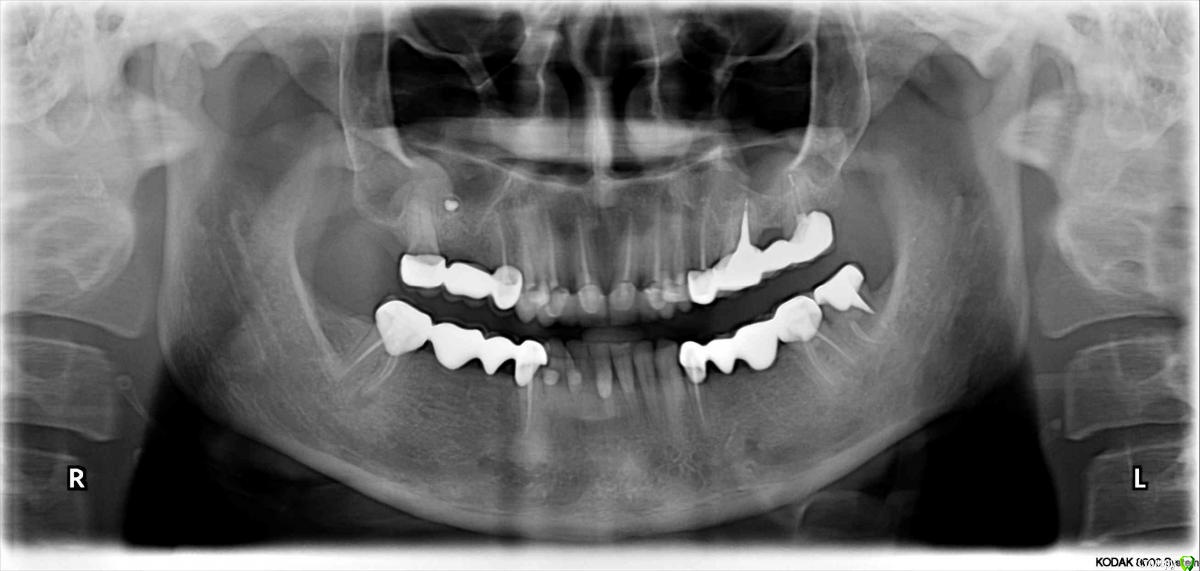

lazzal Опубликовано 29 октября, 2015 Поделиться Опубликовано 29 октября, 2015 Уважаемые хирурги-имплантологи, подскажите пожалуйста возможна ли в моем случае имплантация отсутствующих зубов верхней челюсти, какими имплантами (может мини?) и какая должна быть подготовка -может костная пластика? и возможна ли она? прилагаю 3 панорамных снимка - первый сделан в 2012 году сразу после протезирования всех зубов (делали одномоментно и верх и низ - половина зубов была абсолютно здорова, поднимали прикус таким образом, линия улыбки - безметалловая керамика), второй в апреле 2014г до удаления зуба на в.ч., третий в октябре 2015 (3 дня назад). От чего может быть такая убыль костной ткани? врач говорит, что теперь только бюгельный протез, может он с такими случаями не сталкивался? Возможно, опытные врачи на этом форуме увидят еще какие-то проблемы с зубами или деснами, на которые стоит обратить внимание. мне всего 32 года, я очень симпатичная внешне, очень хочется продлить жизнь своим зубам и не иметь проблем с жеванием. Заранее огромное спасибо всем откликнувшимся, буду Вам безмерно благодарна. Ссылка на комментарий